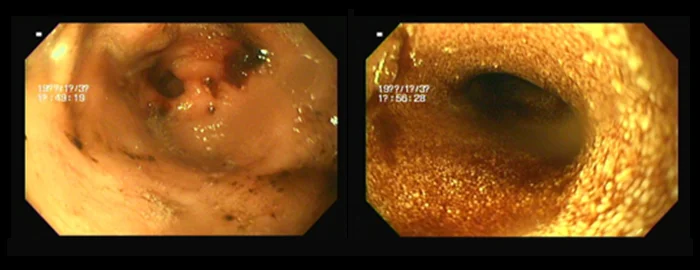

2. 내시경 검사 (Endoscopy)

위장관 내부를 직접 관찰하여 염증, 궤양, 종양 등의 병변을 진단합니다. 필요시 조직 생검을 통해 정확한 병리학적 평가가 가능합니다.

(예: 간염 환자의 경우, 협진을 통해 복강경 생검 고려) 이물 제거 등 치료적 시술도 일부 가능합니다.

• 만성 구토와 설사로 내원한 반려견, 내시경 및 조직검사를 통해

염증성 장질환(IBD) 진단 후 맞춤 식이 및 약물 관리로 증상 개선

수개월간 지속된 소화기 증상으로 고생하던 OOO(환자명)은 정밀 검사를 통해 IBD로 진단받았습니다. 이후 전문적인 내과 관리 프로그램을 통해

구토와 설사 증상이 현저히 개선되었으며, 현재 꾸준한 관리로 건강한 생활을 유지하고 있습니다.